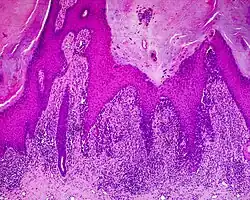

Histology

The main characteristic of acral lentiginous melanoma is continuous proliferation of atypical melanocytes at the dermoepidermal junction.[23] Other histological signs of acral lentiginous melanoma include dermal invasion and desmoplasia.[24] This invasion usually occurs many years after the initial lesion first appears.[7]

According to Scolyer et al.,[25] ALM "is usually characterized in its earliest recognisable form as single atypical melanocytes scattered along the junctional epidermal layer".